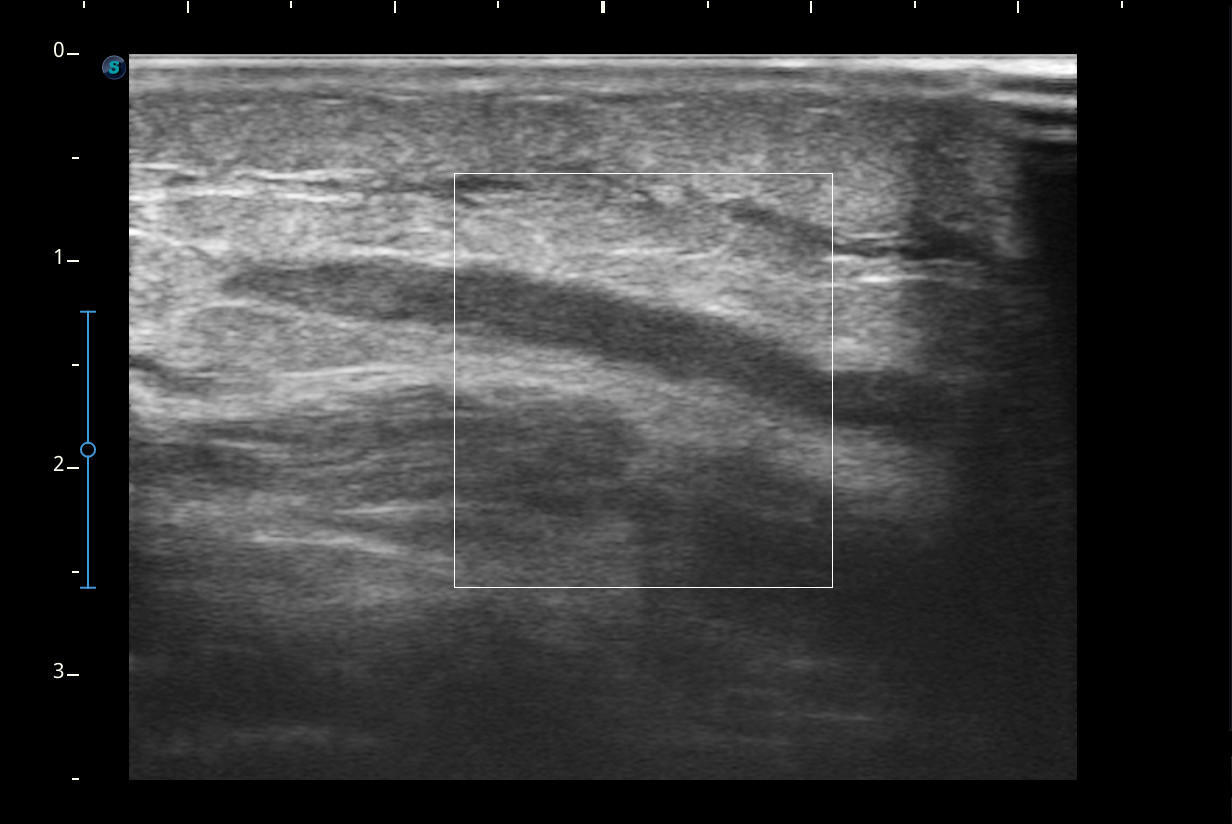

Hallazgos ecográficos

Se visualiza congestión del tejido subcutáneo del brazo y ocupación de la luz de la vena basílica del brazo por un trombo.